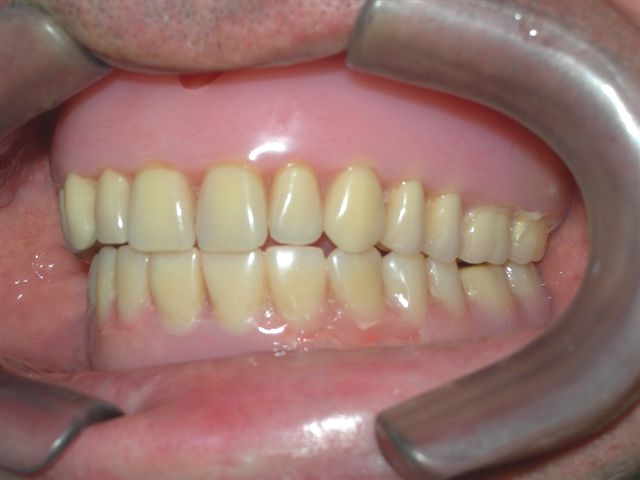

Vista interna da articulação entre as próteses antagonistas |